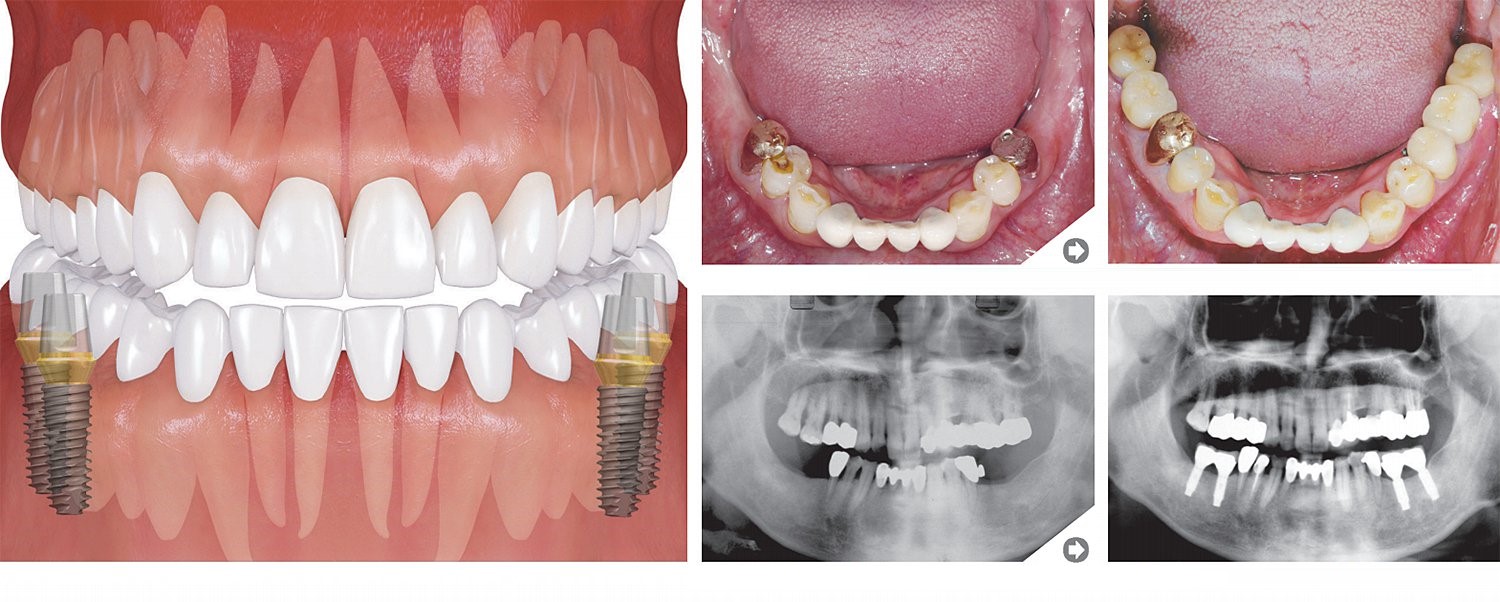

Trūkst pāris zobu

Augšējie molāri

Apakšējie molāri